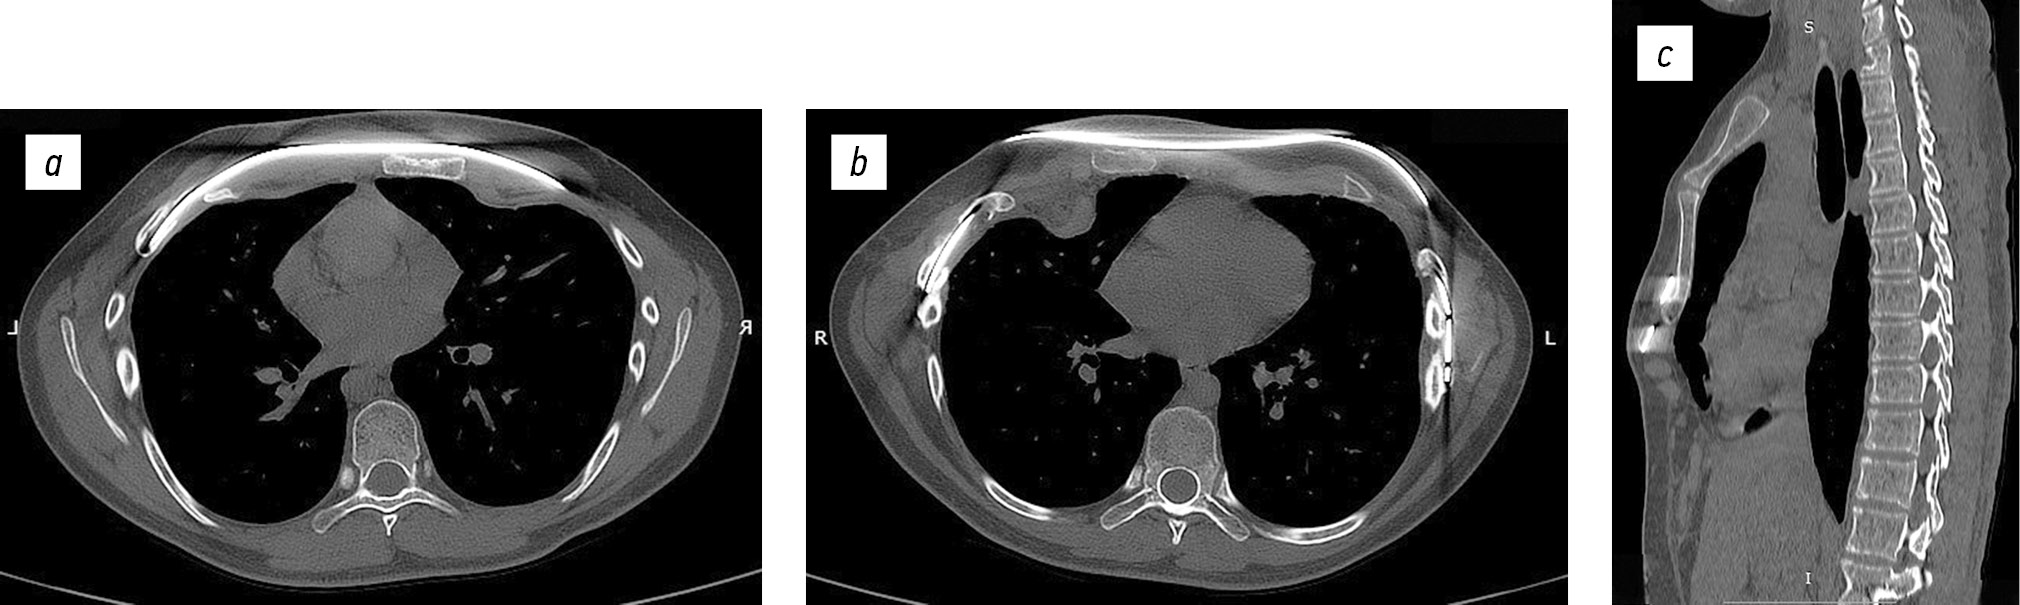

Через сутки от операции в условиях реанимационного отделения и на 5-е сутки выполнена рентгенография грудной клетки — положение металлических пластин правильное, стабильное, легкие расправлены, их пневматизация не нарушена, очаговых и инфильтративных изменений не выявлено (рис. 3).

Рис. 3. Рентгенограмма грудной клетки: на 1-е (а), на 5-е (b) сутки после оперативного лечения.

На 6-е сутки выполнена КТ грудной клетки — положение металлических пластин стабильное. Небольшое скопление воздуха в верхушке легкого без признаков сдавления. Очаговых и инфильтративных изменений не выявлено (рис. 4).

Рис. 4. Компьютерная томограмма грудной клетки после оперативного лечения: горизонтальная плоскость (а, b), сагиттальная плоскость (c). Индекс Галлера 2,19, угол ротации грудины 3° — симметричная, индекс компрессии 0,8.